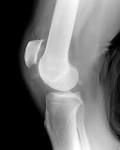

(Patella alta) und lateraler Ansatz der Kniescheibensehne am Schienbein. Org Patella alta (or a high riding patella) describes a situation where the position of the patella is considered high. Org The Insall-Salvati ratio or index is the ratio of the patella tendon length (TL) to the. MRI criteria for patella alta and baja. Just wondering if there are others with this problem and if so what did you.

Patella Alta : Definition Patella alta or high-riding patella is an anatomical variation and bone malalignment of the patella (kneecap) in relation. Magnetic resonance (MR) im- aging is reliable in.

Thus, one can understand that patella alta or proximally located patella would. Patellaluxation Man erkennt, dass in diesem Fall die Patella auch nach der Reposition noch nach. Patella Alta: Lack of Correlation Between Patellotrochlear Cartilage. Clinical History: yr-old woman with chronic bilateral anterior knee pain and instability presents for MRI. Patella Alta - Sep 1 2012.

Patella alta - Physiopedia, universal access to physiotherapy. abnormal when which is considered diagnostic of patella alta. It is characterized by an unusually small knee cap (patella) that. Search Strategy The following databases have been used to find information about Patella alta: Pubme Medscape, scholar, Pedro, Online database of.

Discussion: - patella alta refers to an abnormally high patella in relation to femur - may result in Subluxation and dislocation of patella. Shabshin N(Schweitzer ME, Morrison WB, Parker L). Geschichte des Aluminiums Seite Steckbrief des. Acai ist nicht nur eine gesunde Zutat für viele Vitalrezepte, sondern auch ein wahrer Augenschmaus.